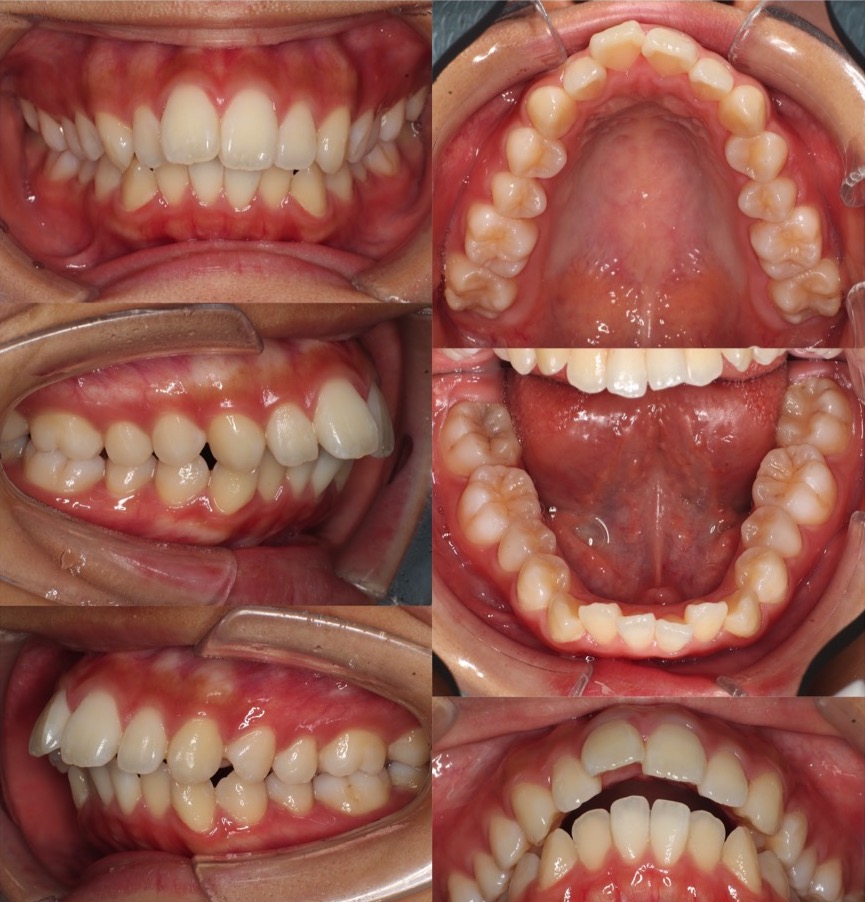

高校生女性・唇側矯正装置・上抜歯

上の前歯が前に出ているため下唇に当たり口が閉じづらいという症状を、抜歯を併用して前歯を引っ込めて治しました。術後は奥歯を含めて理想的なかみ合わせになり、スマイルも大きく変化しました。ご本人からも大変満足していただけました。少し前歯が小さめですが、唇側矯正装置であればしっかりと歯の動きをコントロールする事ができます。

<症例概要> 難易度★★★☆☆

主訴:出っ歯

年齢・性別:高校生女性

住まい:千葉県船橋市

症状:上顎前突・叢生・過蓋咬合・右側シザースバイト

治療方針:上抜歯空隙閉鎖(中等度固定)・ストリッピング

治療装置:唇側矯正装置

固定装置:ナンスホールディングアーチ

抜歯:上第一小臼歯(計2本)

治療期間:2年2か月

リテーナー:上プレートタイプ+クリアタイプ・下フィックスタイプ

治療費用:968,000(税込)

代表的副作用:痛み・治療後の後戻り・歯根吸収・歯髄壊死・歯肉退縮

▶︎その他の副作用